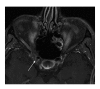

Orbital inflammatory disease (OID) represents a collection of inflammatory conditions affecting the orbit. OID is a diagnosis of exclusion, with the differential diagnosis including infection, systemic inflammatory conditions, and neoplasms, among other conditions. Inflammatory conditions in OID include dacryoadenitis, myositis, cellulitis, optic perineuritis, periscleritis, orbital apicitis, and a focal mass. Sclerosing orbital inflammation is a rare condition with a chronic, indolent course involving dense fibrosis and lymphocytic infiltrate. Previously thought to be along the spectrum of OID, it is now considered a distinct pathologic entity. Imaging plays an important role in elucidating any underlying etiology behind orbital inflammation and is critical for ruling out other conditions prior to a definitive diagnosis of OID. In this review, we will explore the common sites of involvement by OID and discuss differential diagnosis by site and key imaging findings for each condition.